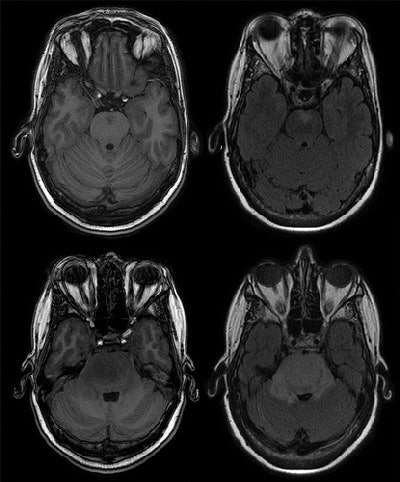

All brain MRI exams were conducted on a 1.5-tesla scanner (GE Healthcare) with identical imaging protocols for all participants at each time point of the study.

The most common incidental finding was meningioma (143, 2.5%), a benign brain tumor that most often occurs in adults, followed by cerebral aneurysms (134, 2.3%). The two abnormalities accounted for more than half of all incidental findings.

"This may partly be from the use of our high-resolution proton density-weighted sequence, which permits a relatively good view of the circle of Willis compared with conventional T1-weighted and T2-weighted sequences and likely improved our detection of aneurysms," they wrote.